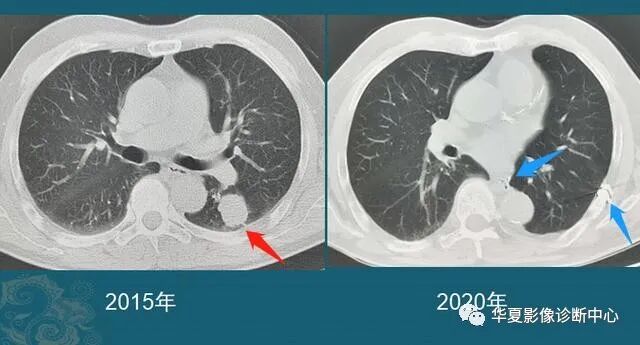

从1个小结节,发展成肺癌,需要几年?看看诊断实例...